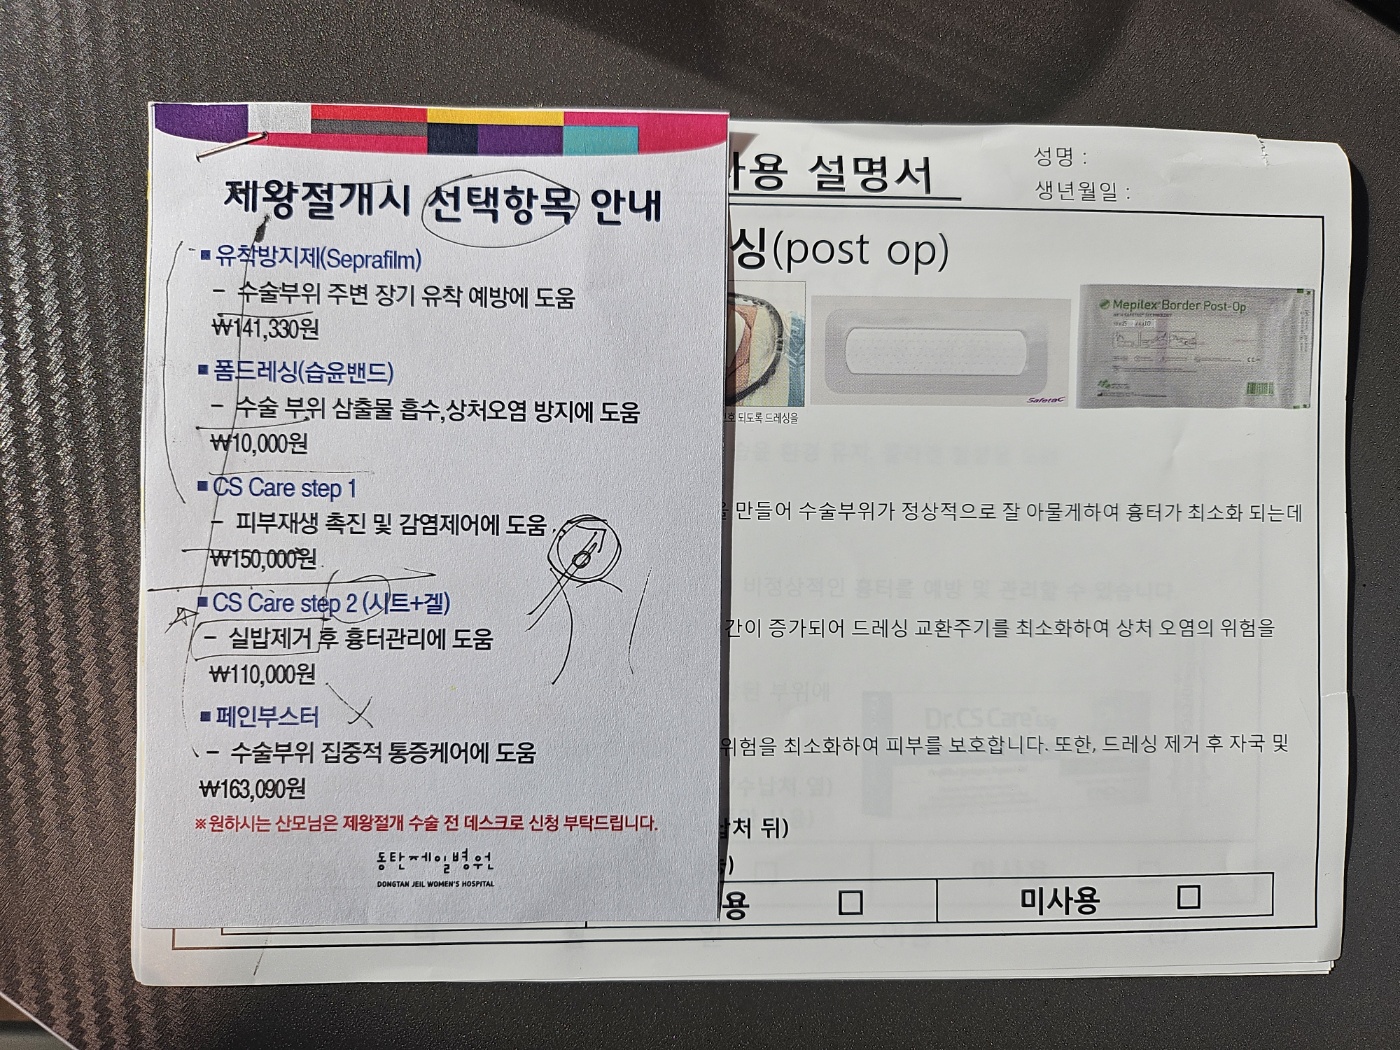

수술 일정, 입원 수속 안내 및 수술시 약제 선택 하기.

제왕절개시 선택항목에 대해 카운터 좌측에 영양제 파는 곳에서 사전 구매 후 출산 당일 날 갖고 가면 된다.

1. 유착방지제 - 담당 간호사에게 알려주면 결제랑 내용물은 출산 시 해줌.

2. 폼드레싱 3장 - 결제함 (출산당일 분만실 준비물, 바우처 안됨)

3. cs care step 1 - 결제함 (출산당일 분만실 준비물, 바우처 안됨)

4. cs care step 2 시트+ 겔 (사전에 아마존 직구로 구매했음. 수술 후 회복기에 필요함)

5. 페인부스터 - 부작용이 많아서 원장님이 안하심.